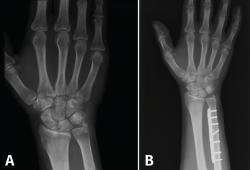

Típicamente, la osteotomía suele ser transversal u oblicua, y la osteosíntesis se lleva a cabo con una placa de compresión (Figura 4). Se realiza una incisión a lo largo del borde subcutáneo del cúbito. La longitud de la incisión está determinada por la longitud de la placa. La disección se lleva a cabo entre el ECU y el flexor carpi ulnaris (FCU). El periostio se incide longitudinalmente y se separa circunferencialmente. La placa debe proporcionar estabilidad y compresión con 3 tornillos bicorticales proximales y distales a la osteotomía. Algunas placas también permiten colocar un tornillo a compresión a través de la osteotomía cuando es oblicua.

Figura 4. A: muñeca con varianza cubital positiva; B: varianza corregida tras osteotomía de acortamiento cubital.